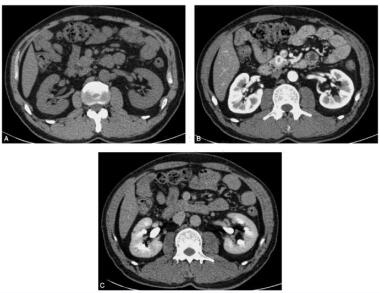

患者,女性,38岁,主诉:上腹部不适1年,体检发现脾脏占位5天。病来患者无腹泻,无呕血及黑便,二便正常。既往否认肝炎病史。查体:皮肤及巩膜无黄染,无局部隆起性包块,全腹软,无压痛,无反跳痛及肌紧张,未触及局部包块,肝脾肋下未及,墨菲征(-),脾区叩痛(+),移动性浊音(-)。CT增强,平扫时脾脏前部可见稍低密度肿块影,与脾脏实质分界欠清楚,动脉期肿块明显强化,高于周围肝实质,门脉期持续强化,高于周围脾脏实质,延迟期强化程度同周围正常组织(图1)。

图1 CT增强扫描:脾脏血管瘤。平扫脾脏前部可见稍低密度肿块影,与脾脏实质分界欠清楚,动脉期肿块明显强化,高于周围肝实质,门脉期持续强化,高于周围脾脏实质,延迟期强化程度同周围正常组织